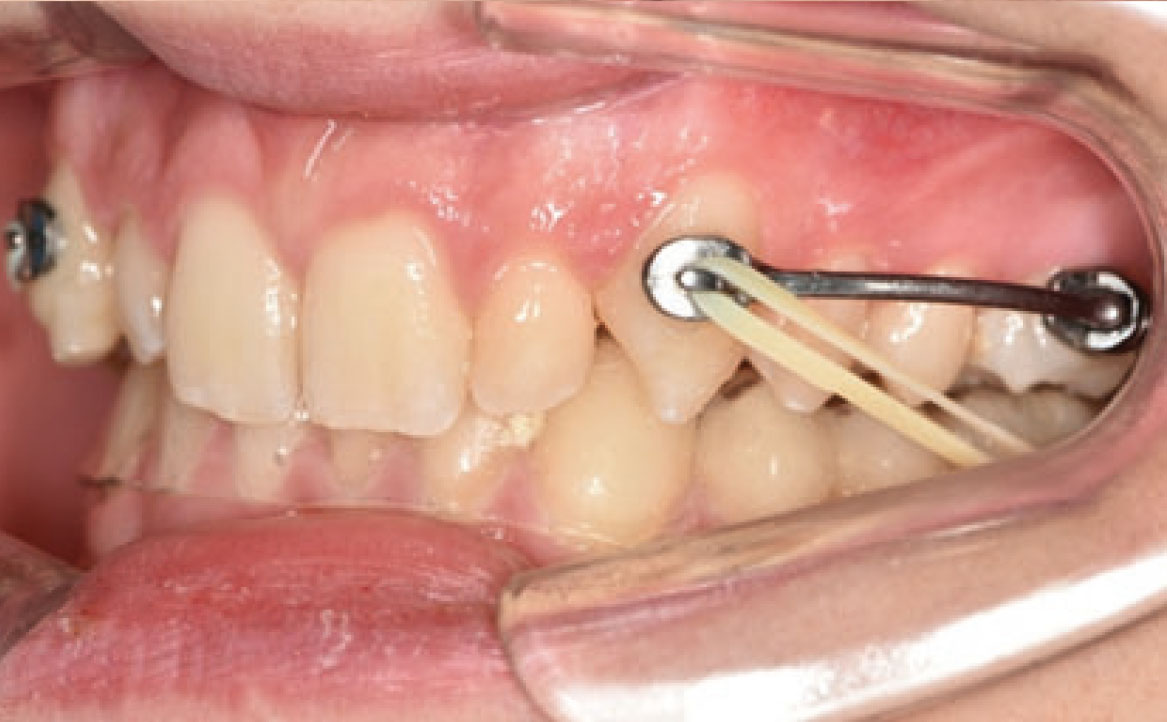

Infatti, durante il primo controllo due mesi dopo, è stato osservato un miglioramento della classe molare (fig. 3a-c).

Un mese dopo, durante il secondo controllo, è stata raggiunta la posizione dei molari richiesta e, di conseguenza, il Carriere Motion è stato sospeso e si è iniziato il trattamento di ortodonzia fissa (fig. 4a-c).